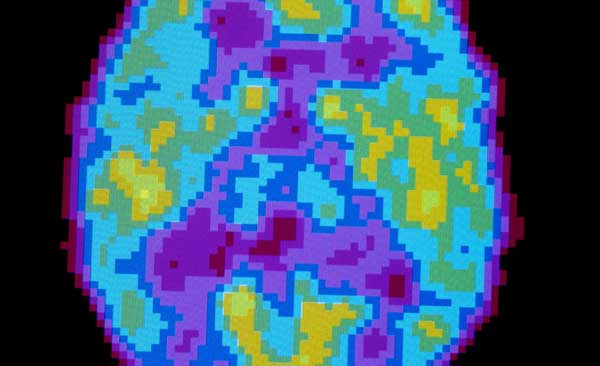

| 关于我们为什么要睡觉,多年来,科学家提出了很多想法。 有些人认为这是一种节约能量的方法。其他人提出,睡眠为大脑提供了清除细胞废物的机会。还有一些人认为,睡眠只是迫使动物静静地躺下来,让它们可以躲过捕食者。 近期,在《科学》(Science)期刊上发表的两篇论文为另一个观念提供了证据:我们睡觉是为了忘记每天所学到的一些东西。 为了学习,我们必须增加大脑神经元之间的连接,或者叫突触。这些连接使神经元能够快速有效地在彼此之间发送信号。我们就是在这些网络之中存储新的记忆。 2003 年,威斯康星大学麦迪逊分校的生物学家朱利奥·托诺尼 (Giulio Tononi) 和基娅拉·奇雷利 (Chiara Cirelli) 提出,突触在白天生长得非常激烈,令大脑电路变得“嘈杂”。当我们睡觉时, 大脑得以减少连接,这样真正的信号才可以超过噪声。 在此之后的几年里,托诺尼博士和奇雷利博士与其他研究者发现了大量间接证据,支持这一所谓的突触自稳态假说。 比如,事实证明,神经元可以修剪它们的突触——至少是在实验室里。在对神经元丛进行实验室实验时,科学家给它们一种药物,刺激它们生长额外的突触。之后,神经元削减了一些生长。 其他证据来自大脑释放的电波。在深度睡眠期间,电波减慢。 托诺尼博士和奇雷利博士认为,这种变化是由突触缩小带来的。 四年前,托诺尼博士和奇雷利博士得以通过观察突触本身来检验他们的理论。他们获得了一种用于脑组织的切片机,用它从小鼠的大脑上得到超薄切片。 该实验室的助理科学家路易莎·德·维沃 (Luisa de Vivo) 对这些从小鼠大脑取出的组织进行了精心研究,一些小鼠是醒着的,其他一些处于睡眠状态。她和同事们确定了 6920 个突触的大小和形状。 他们发现,睡眠小鼠脑中的突触比清醒小鼠的突触小 18%。“整体而言,那个巨大的变化颇为惊人,”托诺尼博士说。 第二项研究由约翰霍普金斯大学博士后研究员格雷厄姆·H·迪林 (Graham H. Diering) 领导。迪林博士和同事们通过研究小鼠脑中的蛋白质来探索突触自稳态假说。“我真的是从这种细节出发来研究这个问题的,”迪林博士说。 在一个实验中,迪林博士和同事们创建了一个小窗口,通过它可以窥看小鼠的大脑。然后,他和同事们在小鼠大脑内添加了一种化学物质,能够点亮脑突触上的表面蛋白。 透过窗口,他们发现,在睡眠期间突触表面蛋白的数量下降。如果突触缩小,这种下降就应该会出现。 迪林博士和同事们随后开始寻找这种变化的分子触发因素。他们发现,在突触内,有数百种蛋白质在夜间增加或减少。但有一种名为 Homer1A 的蛋白质格外突出。 在对神经元进行的早期实验室实验中,Homer1A 被证明在突触减少过程中发挥了重要作用。迪林博士想知道它是否在睡眠中也很重要。 为了发现这一点,他和同事研究了经基因工程改造、不能制造 Homer1A 蛋白的小鼠。这些小鼠可以像普通小鼠一样睡觉,但是它们的突触不像在普通小鼠中那样改变其蛋白质。 迪林博士的研究表明,困倦引发神经元制造 Homer1A,并将其运送到突触。当睡眠开始时,Homer1A 也打开了它的修剪机制。为了观察这种修剪机制如何影响学习,科学家对普通小鼠进行了记忆测试。他们把这些动物放在一个房间里,如果它们走到地板的某一部分,就会受到轻微的电击。 当天晚上,科学家将一种化学物质注入若干小鼠的脑中。在实验室中,这种化学物质已被证明可以阻止神经元减少其突触。 第二天,科学家把所有小鼠都放回之前所在的房间。两组小鼠大部分时间都是一动不动,恐惧地回忆起电击的记忆。 但当研究人员把老鼠放入不同的房间,他们看到了很大的区别。普通组的老鼠好奇地到处嗅着。另一边,在睡眠期间被阻止减少大脑突触的小鼠再次一动不动。 迪林博士认为,受注射的小鼠不能把记忆缩小到它们遭受电击的特定房间范围内。没有夜间的修剪,它们的记忆最后变得模糊。 在他们自己的实验中,托诺尼博士和同事们发现,修剪并不是针对每个神经元。1/ 5 的突触没有改变。有可能这些突触之中编码了已经良好地建立起来、且不应被修改的记忆。 “你可以用一种聪明的方式来忘记,”托诺尼博士说。 其他研究者警告说,新的发现并不能为突触自稳态假说提供决定性的证据。 华盛顿州立大学斯波坎分校的睡眠问题研究者马科斯·G·弗兰克 (Marcos G. Frank) 说,很难判断大脑夜间的变化是由睡眠还是生物钟引起的。“这是该领域的一个普遍问题,”他说。 俄亥俄睡眠医学研究所 (Ohio Sleep Medicine Institute) 的马库斯·H·施密特 (Markus H. Schmidt) 说,虽然大脑可能在睡眠期间修剪突触,但他质疑这一点是否是睡眠存在的主要原因。 “这项工作很好,”他谈起这项新研究时说,“但问题是,这是睡眠的功能之一,还是它的主要功能?” 不仅大脑,许多器官在睡眠时的功能似乎都不一样,施密特博士指出。比如肠道似乎就会产生许多新的细胞。 托诺尼博士说,新的发现可以促使人们审视目前的睡眠药物在大脑中发挥什么作用。虽然它们可以让人们感到困意,但它们也可能干扰形成记忆所需的突触修剪。 “你可能其实是在损害自己,”托诺尼博士说。 在将来,睡眠药物或许可以精确瞄准参与睡眠的分子,确保突触得到适当的修剪。 “一旦你知道一点基本事实层面发生的情况,就可以得到更好的治疗思路,”托诺尼博士说。 原文检索: Luisa De Vivo, Michele Bellesi, William Marshall, Eric A. Bushong, Mark H. Ellisman, Giulio Tononi, Chiara Cirelli. Ultrastructural evidence for synaptic scaling across the wake/sleep cycle. Science, 2017 DOI: 10.1126/science.aah5982 Graham H. Diering, Raja S. Nirujogi, Richard H. Roth, Paul F. Worley, Akhilesh Pandey, Richard L. Huganir. Homer1a drives homeostatic scaling-down of excitatory synapses during sleep. Science, 2017 DOI: 10.1126/science.aai8355 |